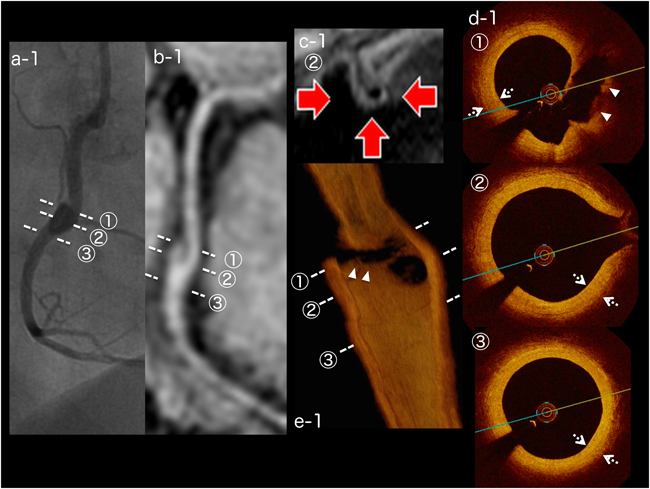

Fig. 1 Image findings for Case 1

Cross-section imaging with the number correspond with the dotted line of the same number . On coronary angiography, the maximum diameter of the aneurysm (segment 2) is 4.5 mm (a-1), and the aneurysm is in the form of a slit on magnetic resonance coronary angiography (b-1). Vessel wall imaging shows thickening at the aneurysm (c-1, arrows). On optical coherence tomography imaging (d-1, e-1), the slit-like aneurysm has separation of the intima (closed triangles), and the intima of this aneurysm is hyperplastic with fibrosis (dashed arrows).